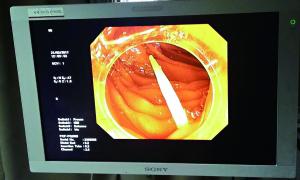

卡在腸道中的牙簽的影像檢查圖。

據中山一院胃腸外科譚進富副主任醫師介紹,胃鏡檢查發現,這根牙簽一路下滑,滯留在小腸,一端刺破腸道,鉆出去的部分占了三分之二長,引發了嚴重感染。